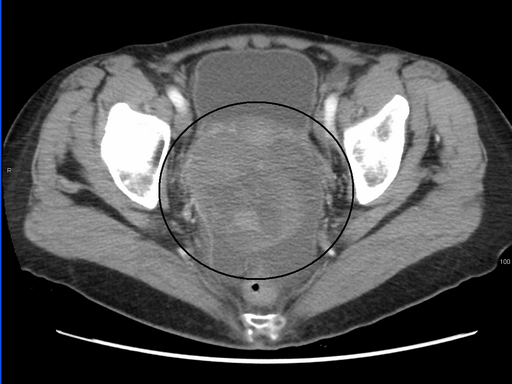

A large ovarian cancer tumour as seen on a CT scan. Photo credit: James Heilman